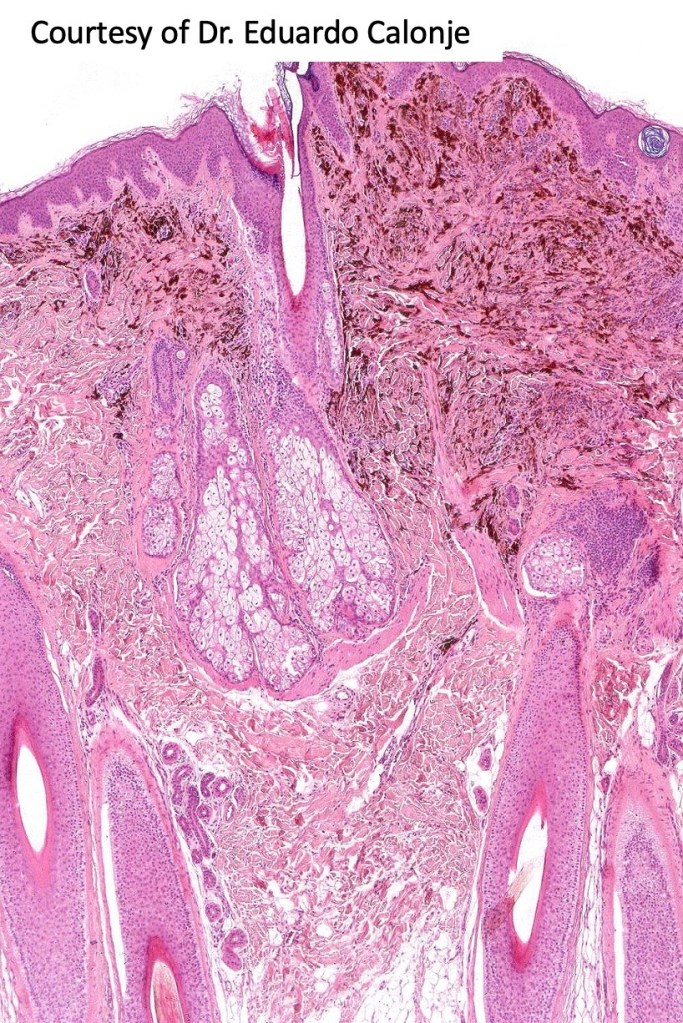

Combined common & deep penetrating nevus